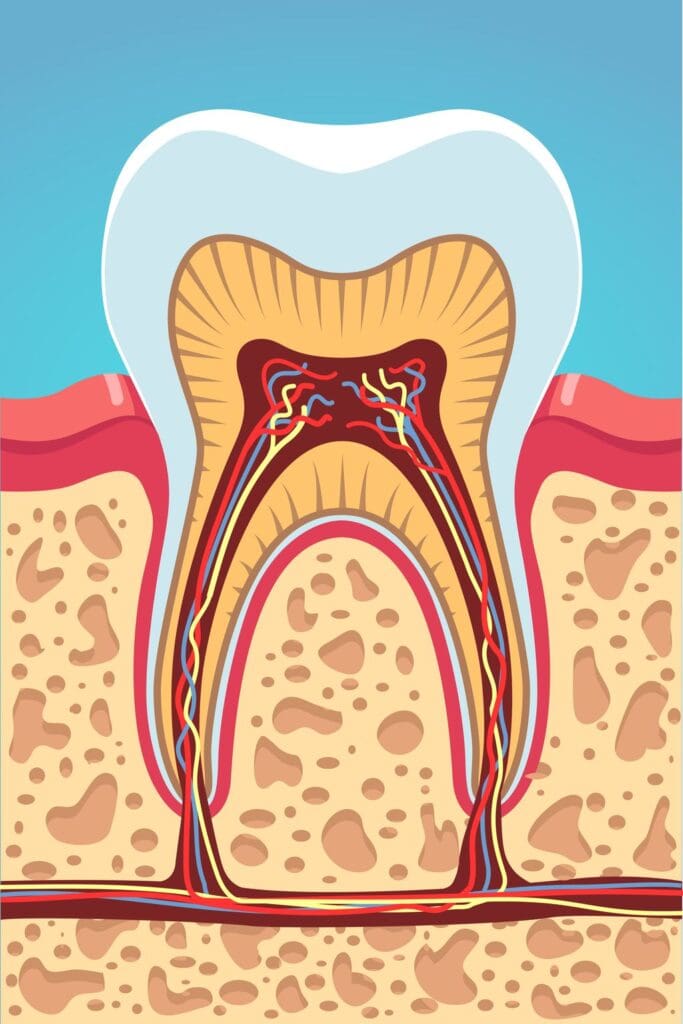

The acids that bacteria excrete can create tiny holes, or caries, in your tooth enamel. Caries are easy to fix. However, once the acids in the bacteria eat their way through your tooth enamel and into the hard dentin below, the dental caries become cavities.

The dentin is not as strong as your tooth enamel, and it will not take the bacterial acid long to eat through it. Once the bacteria and acids reach the middle of your tooth, they cause an infection, which may be the first time you feel pain because the pulp of your tooth is full of nerves. When the cavity reaches the pulp, that is when you need a root canal. However, you may be able to make do with a pulpotomy.

Pulpotomies can be used on baby teeth as well as permanent teeth. In both cases, if the infection inside the tooth is only in the crown – or top- of the tooth, you or your child can have a pulpotomy.

In a pulpotomy, our dentist makes an incision in the top of your tooth and removes the infection, replacing it with composite material. Then, the top of the tooth gets a cap or a crown to keep it strong. This procedure saves the tooth from the infection.